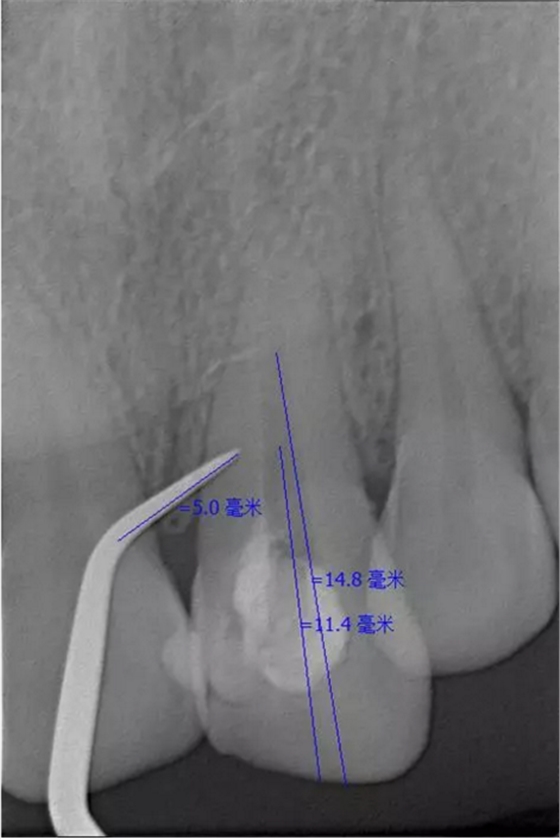

患者女,年齡35左右,牙位21,根管治療曾經(jīng)歷過外院四到五次等不同地方的處理,還是不能咬硬物,會(huì)有酸、軟、痛的情況出現(xiàn),偶有自發(fā)疼痛,2016年9月初,轉(zhuǎn)診至我處治療21。術(shù)前拍片發(fā)現(xiàn)根中部存在側(cè)穿,橡皮障下常規(guī)再治療,隨后減輕了軟和痛的情況。因?yàn)閭?cè)穿,牙周膜受到牙膠尖等異物的持續(xù)刺激,酸軟的情況還是持續(xù)存在,所以決定行根尖外科手術(shù),采用MTA修補(bǔ)穿孔點(diǎn)。術(shù)后觀察半年左右,所有癥狀消除后,隨后熱牙膠充填。

隨訪半年后,癥狀消除,熱牙膠根充